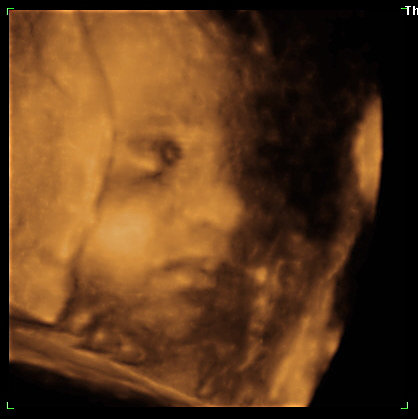

Fanni még farfekvéses 1,2 kg körül mozog és olyan cuki volt, mert a lábait az arca elé húzta és átkarolta őket. Mikor totál megunta, hogy böködik, akkor meg teljesen eltakarta a pofiját és bebújt a méhlepény felé.

na de azért hoztam pár képet!

Kép lábak, kezek és kislányalkatrész Kép az a gyönyörű bokacsont és vádli! Kép és a pofikája